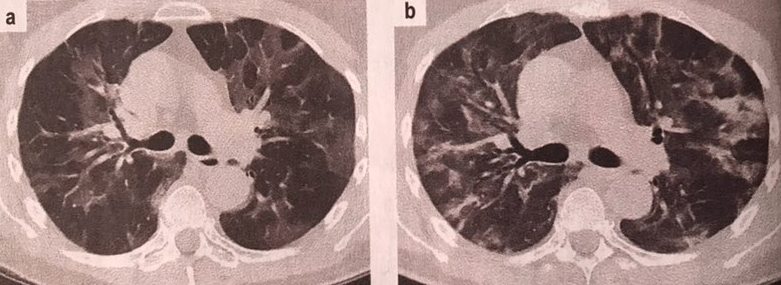

Халдвар авсан тохиолдолд: 80-аас доош хувь нь шинж тэмдэггүй буюу хөнгөн хэлбэрээр өвдөж байна. Гол шинж тэмдэг нь хоолой өвдөх, үе мөч өвдөх, халуурах, үнэрлэх амтлах мэдрэмж алдагдах, мөн гэдэс ходоодоор хямрах, гүйлгэх шинж тэмдэг илэрч байна. Бусад шатанд ихэнх тохиолдолд вирусний гаралтайгаар уушгины үрэвсэл, баруун зүүн уушгинд гэмтэл үүсгэнэ. Ачаалалтай болон тайван үед амьсгаадах, амьсгалын давтамж 1 минутад 30-аас дээш (норм 15 минут) болох мөн цусан дахь хүчилтөрөгчийн хангамж 90-ээс доош хувь (норм 100 хувь)болж байна

Өвчин маш хүнд үедээ ороход: Амьсгалын огцом дутагдал (ARDS) болох, амьсгалын хурц дутагдалд орох, уушги, зүрх, бөөрний дутагдалд орох. Эдгээр нь нас баралтын гол шалтгаан болж байна.

3. Уушгины рентгэн буюу компьютер томаграфик